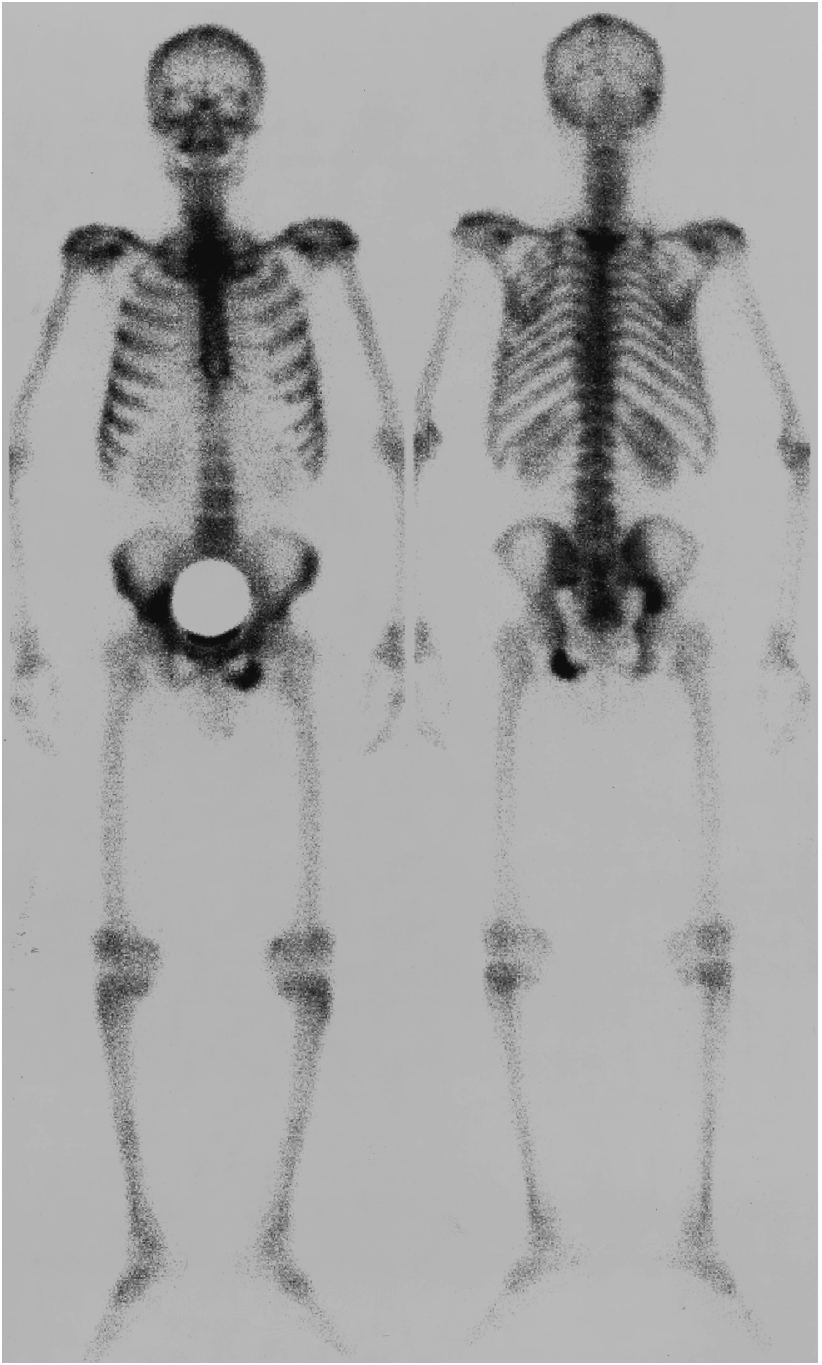

全身骨シンチグラフィ 乳癌 肺癌 前立腺癌等の骨転移病巣の検出

全身骨シンチグラフィ 乳癌 肺癌 前立腺癌等の骨転移病巣の検出

骨シンチグラフィによる骨転移の診断 Bone Scan Ct Mri画像診断